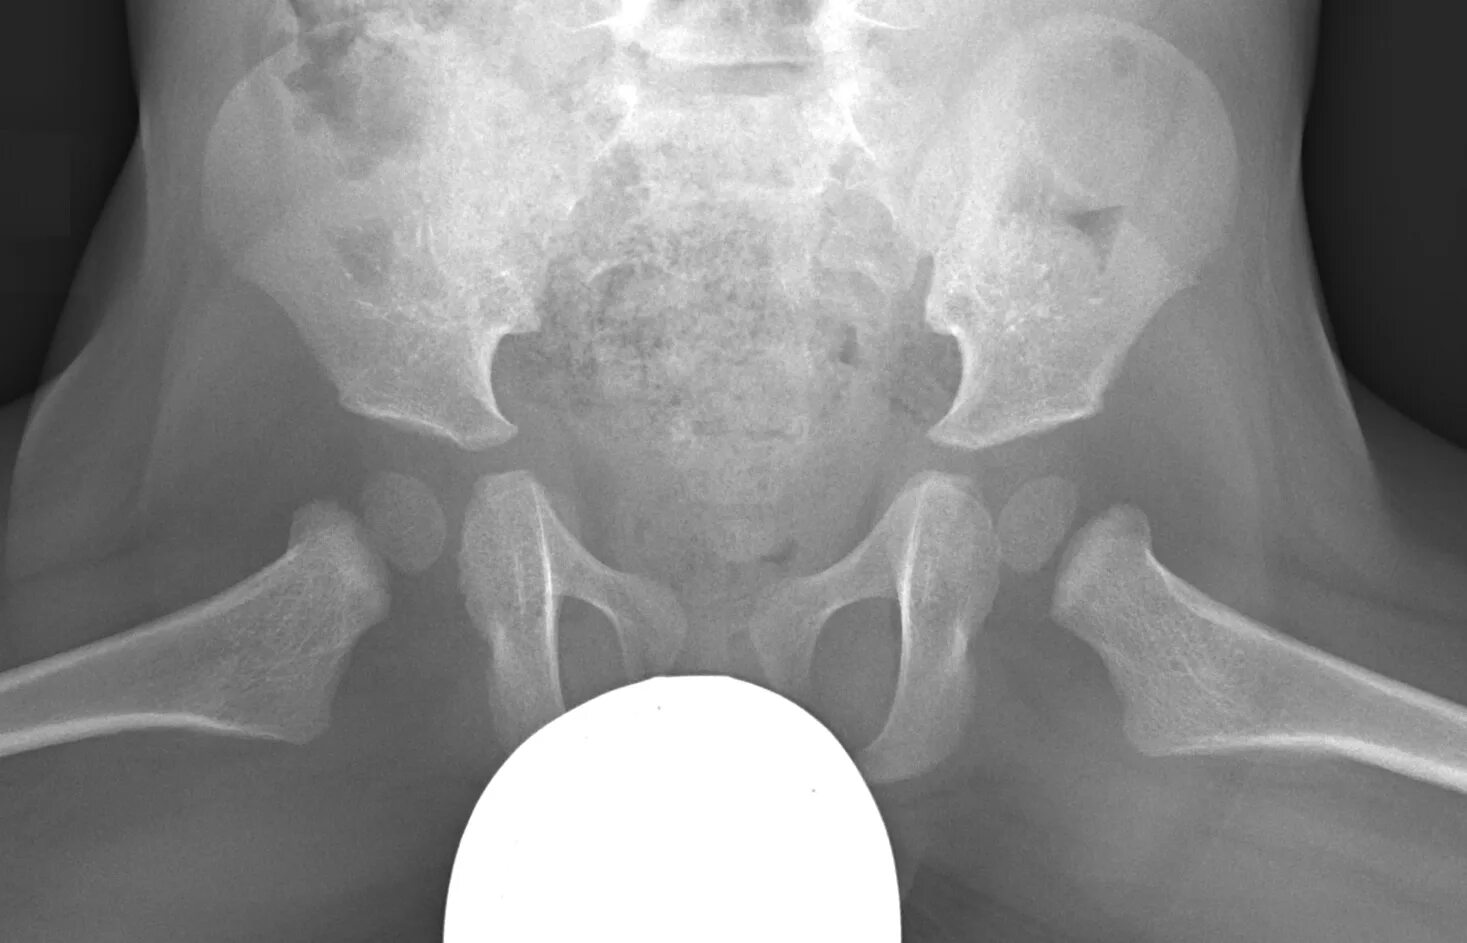

Проекции рентгена тазобедренного сустава